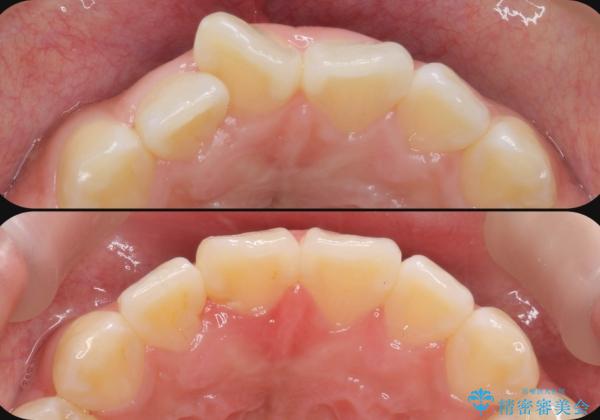

- 前歯の目立つねじれを矯正治療で治したい、と来院されました。

マウスピース矯正を始める前に、ねじれを取るのが短期間で済む部分ワイヤー小矯正を行うことで、全体的な治療期間を短くする治療計画を実行していきます。

前歯のねじれはマウスピース矯正の苦手な動きになり、治療期間が長くなる原因になりやすいです。